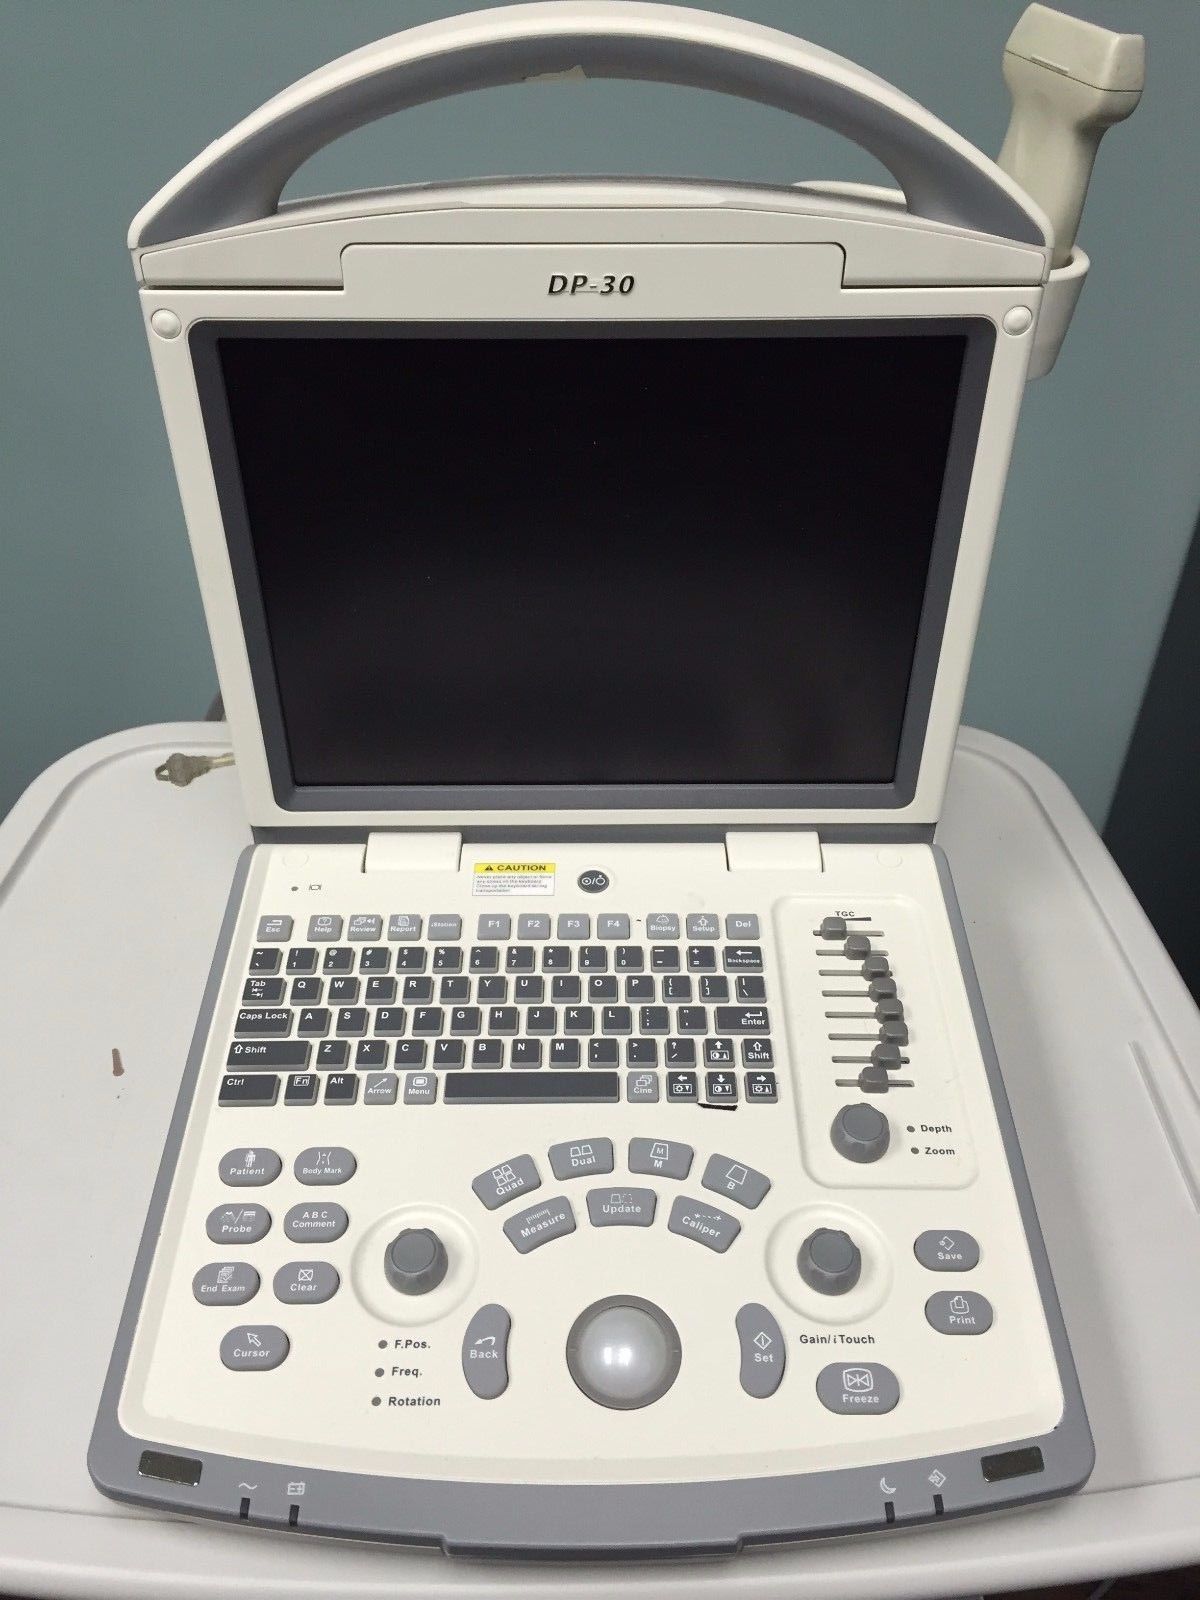

DIAGNOSTIC ULTRASOUND MACHINES FOR SALE

Mindray DP-30 Ultrasound Diagnostic Imaging Device

Sale price$ 17,549.99

Save $ 400.00